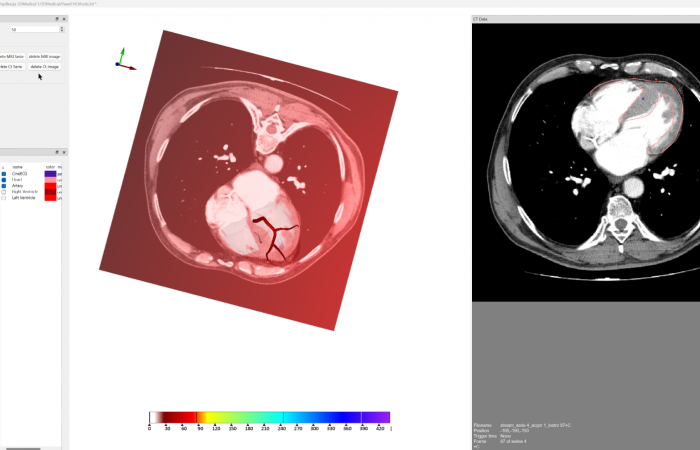

Pracownia Funkcjonalnego i Wirtualnego Medycznego Obrazowania 3D

(ang. Laboratory of Functional and Virtual Medical 3D Imaging, akronim: 3D-vFMi(maging), skrót: 3D-FM)

Pracownia Funkcjonalnego i Wirtualnego Medycznego Obrazowania 3D (Pracownia 3D-FM) funkcjonuje w strukturze Zakładu Diagnostyki Obrazowej Szpitala Uniwersyteckiego w Krakowie pod kierownictwem Prof. dr hab. Tadeusza Popieli. Jej celem jest opracowanie i wdrożenie innowacyjnych metod przetwarzania oraz analizy sygnałów i obrazów medycznych, w tym wykorzystanie technologii rzeczywistości wirtualnej oraz metod obrazowania funkcjonalnego. Rozwiązania te wspierają przedoperacyjne planowanie, monitorowanie procedur medycznych oraz wzbogacają proces diagnostyczny o nowe formy wizualizacji danych medycznych.

Zakres działalności

Pracownia 3D-FM zajmuje się m.in. następującymi obszarami:

- Tworzeniem modeli 3D do celów przedoperacyjnego planowania oraz wizualizacji diagnostycznej.

- Rozwojem rozwiązań programowych do obrazowania medycznego.

- Integracją urządzeń i systemów diagnostycznych (PACS, RIS, HIS, OIS) z infrastrukturą szpitalną, umożliwiającą efektywne zarządzanie danymi obrazowymi i funkcjonalnymi.

- Oceną jakości i poprawności danych medycznych w celach wizualizacji przestrzennych oraz optymalizacją protokołów akwizycji i konfiguracją urządzeń do tych celów.

- Współpracą z jednostkami organizacyjnymi Szpitala Uniwersyteckiego oraz partnerami zewnętrznymi.

- Poszukiwaniem nowych możliwości rozwoju w zakresie funkcjonalnego i wirtualnego obrazowania medycznego 3D.

- Analizą biostatystyczną danych medycznych i edukacja w zakresie nowych technologii.

Obszary badawcze

- Obrazowanie Medyczne 3D

- Segmentacja i analiza danych DICOM

- Rekonstrukcja danych medycznych

- Technologie immersyjne (mieszana, rozszerzona i wirtualna rzeczywistość)

- Obrazowanie funkcjonalne

- Analiza surowych danych biologicznych

- Analiza sygnałów z czujników (np. kamera 3D, przenośny analizator oddechu „Sniffer”)

- Elektrokardiograficzne obrazowanie 3D (ECGI)

- Modelowanie fizjologiczne

- Analiza sygnałów czasowych, w tym EKG

- Projektowanie i konstrukcja mechaniczna

- Analiza danych medycznych i edukacja

- Programowanie i metody statystyczne (w tym AI) w analizie danych medycznych

- Zarządzanie danymi

- Opracowanie kursów edukacyjnych dla studentów, lekarzy, rezydentów i doktorantów

- System zintegrowanych kwalifikacji

Pracownia Funkcjonalnego i Wirtualnego Medycznego Obrazowania 3D łączy nowoczesne technologie z praktycznym zastosowaniem w diagnostyce i terapii. Dzięki interdyscyplinarnej współpracy oraz zaawansowanym narzędziom badawczym dążymy do podnoszenia standardów opieki medycznej w Szpitalu Uniwersyteckim w Krakowie.